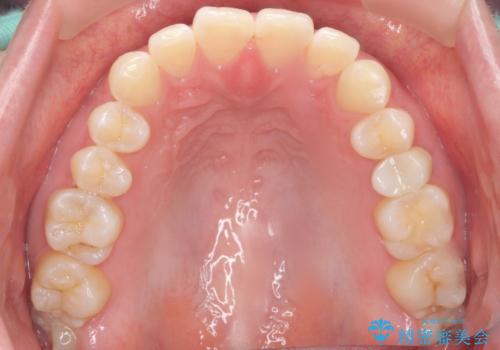

精査したところ、左上の小臼歯(左上5)は被せ物がないまま放置していたことにより、両隣の歯が寄ってきてスペースが少なくなり、また隣の歯(左上4)も虫歯になっていました。

隣の歯の虫歯治療(保険内のレジン充填)後、セラミッククラウンによる補綴を行いました。

仮歯およびクラウンの仮付け期間を設け、はずれにくいことや咬み合わせに問題がないことを確認した上で本付けを行いました。

ホワイトニングも行い、口元の印象が明るくなりました。

クラウンの種類:オールセラミッククラウン スタンダード